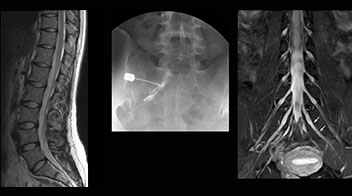

“Before NerveVIEW, diagnosis by MRI alone was sometimes difficult, unless there was a strong suspicion based on clinical symptoms,” says Shoji Yabuki, MD, DMSc, Orthopedic surgeon at Fukushima Medical University School of Medicine. “This is why we routinely perform selective lumbosacral radiculography (nerve root block) and x-ray in such cases. However, radiculography can only depict nerves as far as the contrast agent reaches. When a nerve is distorted by compression, the contrast agent will not pass through this compressed area, preventing us from evaluating the full nerve compression.”

“In such case, we would then browse through axial T2-weighted MR images slice by slice and mentally reconstruct the actual situation based on both radiculography and MRI. Fortunately, NerveVIEW can now very well show nerve courses and presence of nerve compression or edema in one single image series.”

“We have often seen NerveVIEW directly depict details of the nerve compression that were not observed by radiculography. Therefore, we think that with NerveVIEW we can reduce the number of invasive examinations, especially for some patients with lumbar plexus symptoms.”

The key concept in MR neurography, Dr. Yabuki stresses, is the ability to directly visualize spinal nerves, versus inferring the presence of pathology indirectly. “Before NerveVIEW, we estimated compression of the nerve by looking for the presence or absence of fat signal on other MR images,” he says.

“For example, in sagittal images, when the presence of fat is observed in the intervertebral foramen, it suggests that there is a margin around the nerve. Similarly, the absence of fat indicates that the nerve is being compressed. So, we used to deduce nerve compression indirectly. With NerveVIEW, however, we can observe the condition of the nerves directly, regardless of the presence or absence of fat. We always prefer such direct observation of anatomy over having to make an inference about it.”

Distinguishing typical from atypical herniation informs the surgeon

“NerveVIEW is really useful for those cases where a nerve disorder is strongly suspected based on the clinical examination but our regular MRI images do not show any findings. These atypical herniations and spinal canal stenosis, occurring in 5% to 15% of the total lumbar herniation/stenosis cases are our main target when using NerveVIEW,” says Dr. Yabuki.

“Although symptoms of typical disc herniation and atypical hernia are very similar, the actual site of herniation is different. It is therefore important to characterize the nerve’s condition both inside and outside of the intervertebral foramina.

“Conversely, if we see no abnormality in NerveVIEW, we can assume at least that there is no severe condition that requires surgery. Like this, it can help us avoid unnecessary surgery. NerveVIEW can have a tremendous impact in this way.”